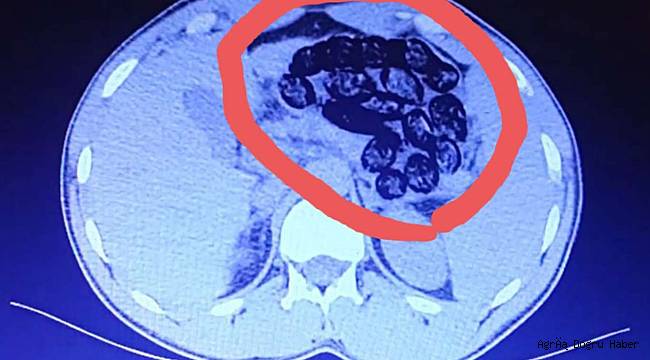

Van Emniyet Müdürlüğünden yapılan açıklamada, Narkotik Suçlarla Mücadele Şube Müdürlüğü görevlilerince yapılan risk analizi çalışmaları neticesinde İran uyruklu A.D. ve S.A. isimli şahıslardan şüphelenildiği belirtilerek, “Şahısların Van-İzmir uçağına binişleri engellenmiş, alınan karara istinaden yapılan iç beden muayenesinde şahısların midelerinde kapsül halinde yabancı cisimler olduğu görülmüştür. Şahıslar yapılan iç beden muayenelerinden sonra taburcu edilmişler ve A.D'den 52 adet kapsül halinde 460 gram, S.A'dan ise 51 adet kapsül halinde 460 gram olmak üzere toplamda 103 adet kapsül halinde 920 gram metamfetamin maddesi ele geçirilmiştir. Elde edilen uyuşturucu maddeyle ilgili olarak gözaltına alınan A.D. ve S.A. isimli şahıslar, sevk edildikleri adli makamlarca tutuklanmışlardır.” denildi. (İLKHA)

2 İranlının yapılan muayenesinde, toplamda 103 adet kapsül halinde 920 gram metamfetamin maddesi ele geçirildi.